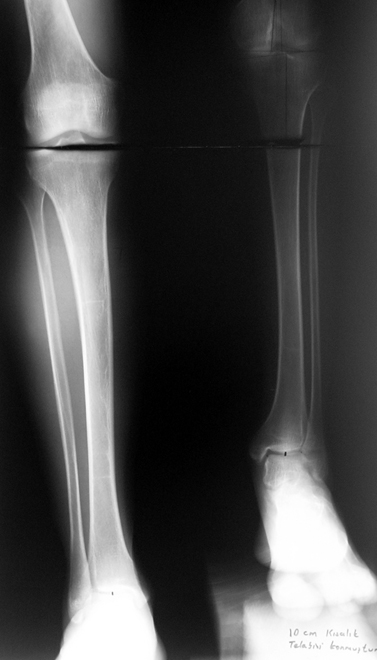

3. POSTTRAUMATIC LOWER LIMB SHORTNESS (MALUNION)

This type of shortness occurs after a fracture heals in a shortened position. Most cases are seen in adults and can be treated with one lengthening operation. Additional deformities can be corrected simultaneously. Most of these cases can be treated with lengthening over nail or just corrections and intramedullary nailing.